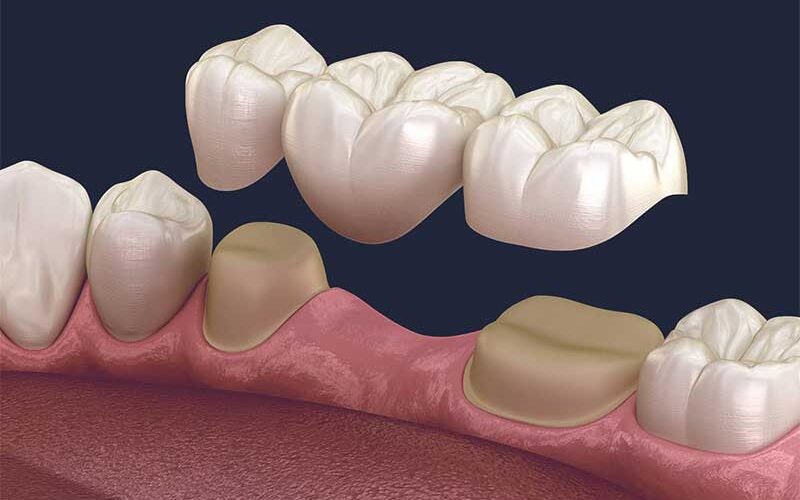

Diş eksikliklerinde başka bir tedavi alternatifi de köprü yapmaktır.Çekilen dişinizin bulunduğu bölgede kemik yapısı implant tedavisi için uygun değilse ya da maddi sebeplerden dolayı implant tedavisi yaptıramıyorsanız ve sabit dişlerim olsun istiyorsanız o zaman köprü yaptırabilirsiniz.

Köprü yapmak için belirli kurallar vardır ve hekiminiz detaylı bir muayeneden sonra endikasyon verebiliyorsa köprü tedavisi yaptırabilirsiniz.